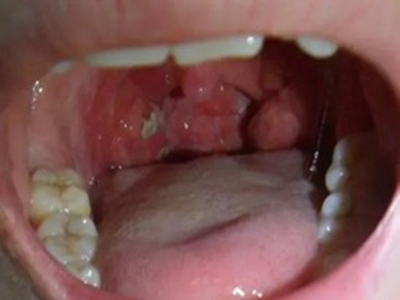

扁桃体结石是指发生在扁桃体隐窝的结石,是扁桃体隐窝细胞聚集所致的灰白色钙化团,扁桃体结石临床较少见。

扁桃体结石多呈灰白色,表面粗糙,质地坚硬。部分患者可自觉咽部有异物,结石较大者,进食可出现阻挡感。并发扁桃体炎症时,可出现患侧扁桃体肿大、咽痒、刺激性咳嗽等症状,甚则可出现咽喉肿痛、吞咽困难、发热等全身症状。

扁桃体内可发现灰白色、质地较硬的细小沙石,或可在肿大的扁桃体内触及较硬的肿块,触时有微痛感。